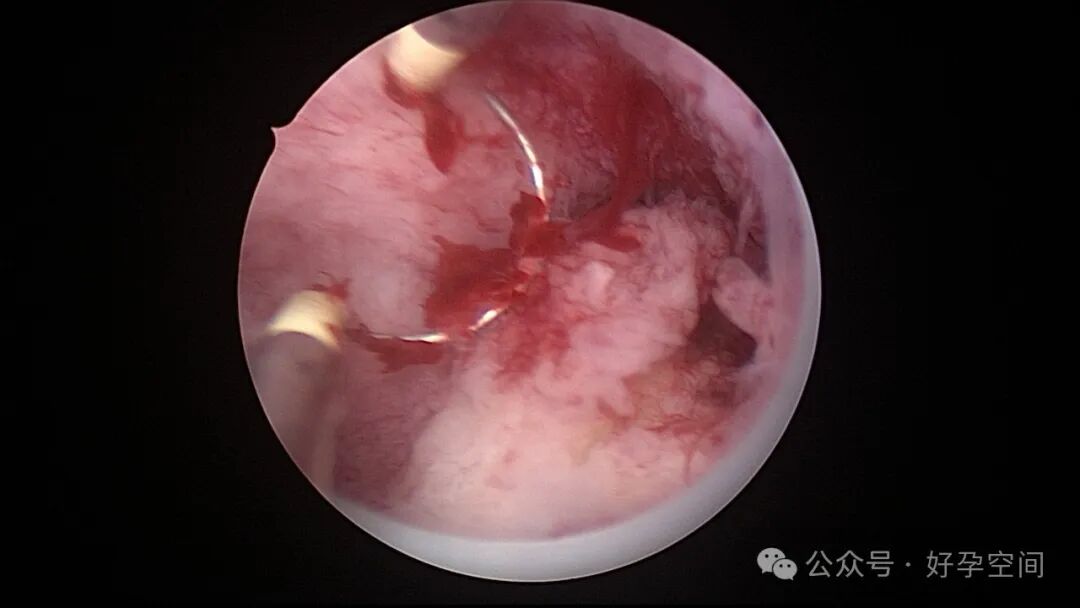

患者24岁,G6P3,顺产1次,双胎剖宫产1次。本次停经53天,计划外妊娠,行宫腔镜取胚及安环术。摘除胚胎后见宫腔右侧壁胚胎附着部位包块,约1.0cm*1.0cm*0.8cm,宫腔镜切除包块送病检,放置γ环一个,环两臂卷曲于右侧宫角,宫腔镜钩住环尾部下拉,上推节育环右臂,将环调整到正常位置。术后病检结果为“宫腔胎盘附着部位超常反应”。

超常胎盘部位(exaggerated placental site,EPS)反应是指在胎盘附着部位组织的过度反应性病变。1991年,WHO将其列入滋养细胞疾病,但目前国内外对该病的诊断尚无统一标准。在正常妊娠中,中间型滋养细胞可侵入底蜕膜或浅肌层,而超常胎盘部位反应时,中间型滋养细胞在胎盘部位大量浸润,并侵入子宫肌层,是正常胎盘反应的加剧,是一种滋养细胞疾病。EPS反应可发生于正常妊娠、流产或葡萄胎后,发生于葡萄胎者浸润力更为明显。EPS以病理诊断为依据,其组织学特征以中间型滋养细胞为主,由子宫内膜向肌层的良性漫润,不破坏原有组织结构,伴有淋巴细胞灶性浸润。EPS是一种非肿瘤性的良性滋养细胞疾病,普通人工流产、宫腔镜取胚或产后出血增多,手术医生主观感觉宫腔已经清理干净,但B超提示宫内占位包块,应考虑到是否存在EPS,建议做宫腔镜探查,切除包块送病检,以明确诊断,避免遗漏其他严重疾病,EPS对症治疗即可,观察病情变化,预后良好。